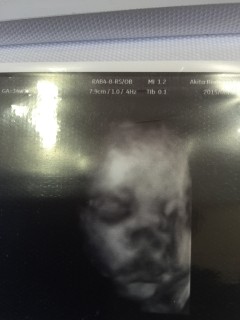

初産婦です。 2316gの推定女の子。 おちんちん隠してたら分からないけど 3回聞いて全部女の子って言ってたから 女の子と信じてます(笑) 前回までハッキリ見せてくれなかった顔を やっと見せてくれました。写真がボヤけててどっち似かは不明ですが可愛いです♡

初めての4Dエコー。お顔をハッキリ見せてくれました(*^^*)本当に感動しました!2400gでスクスクに育ってくれてます。 後1ヶ月ちょっと!楽しみです。